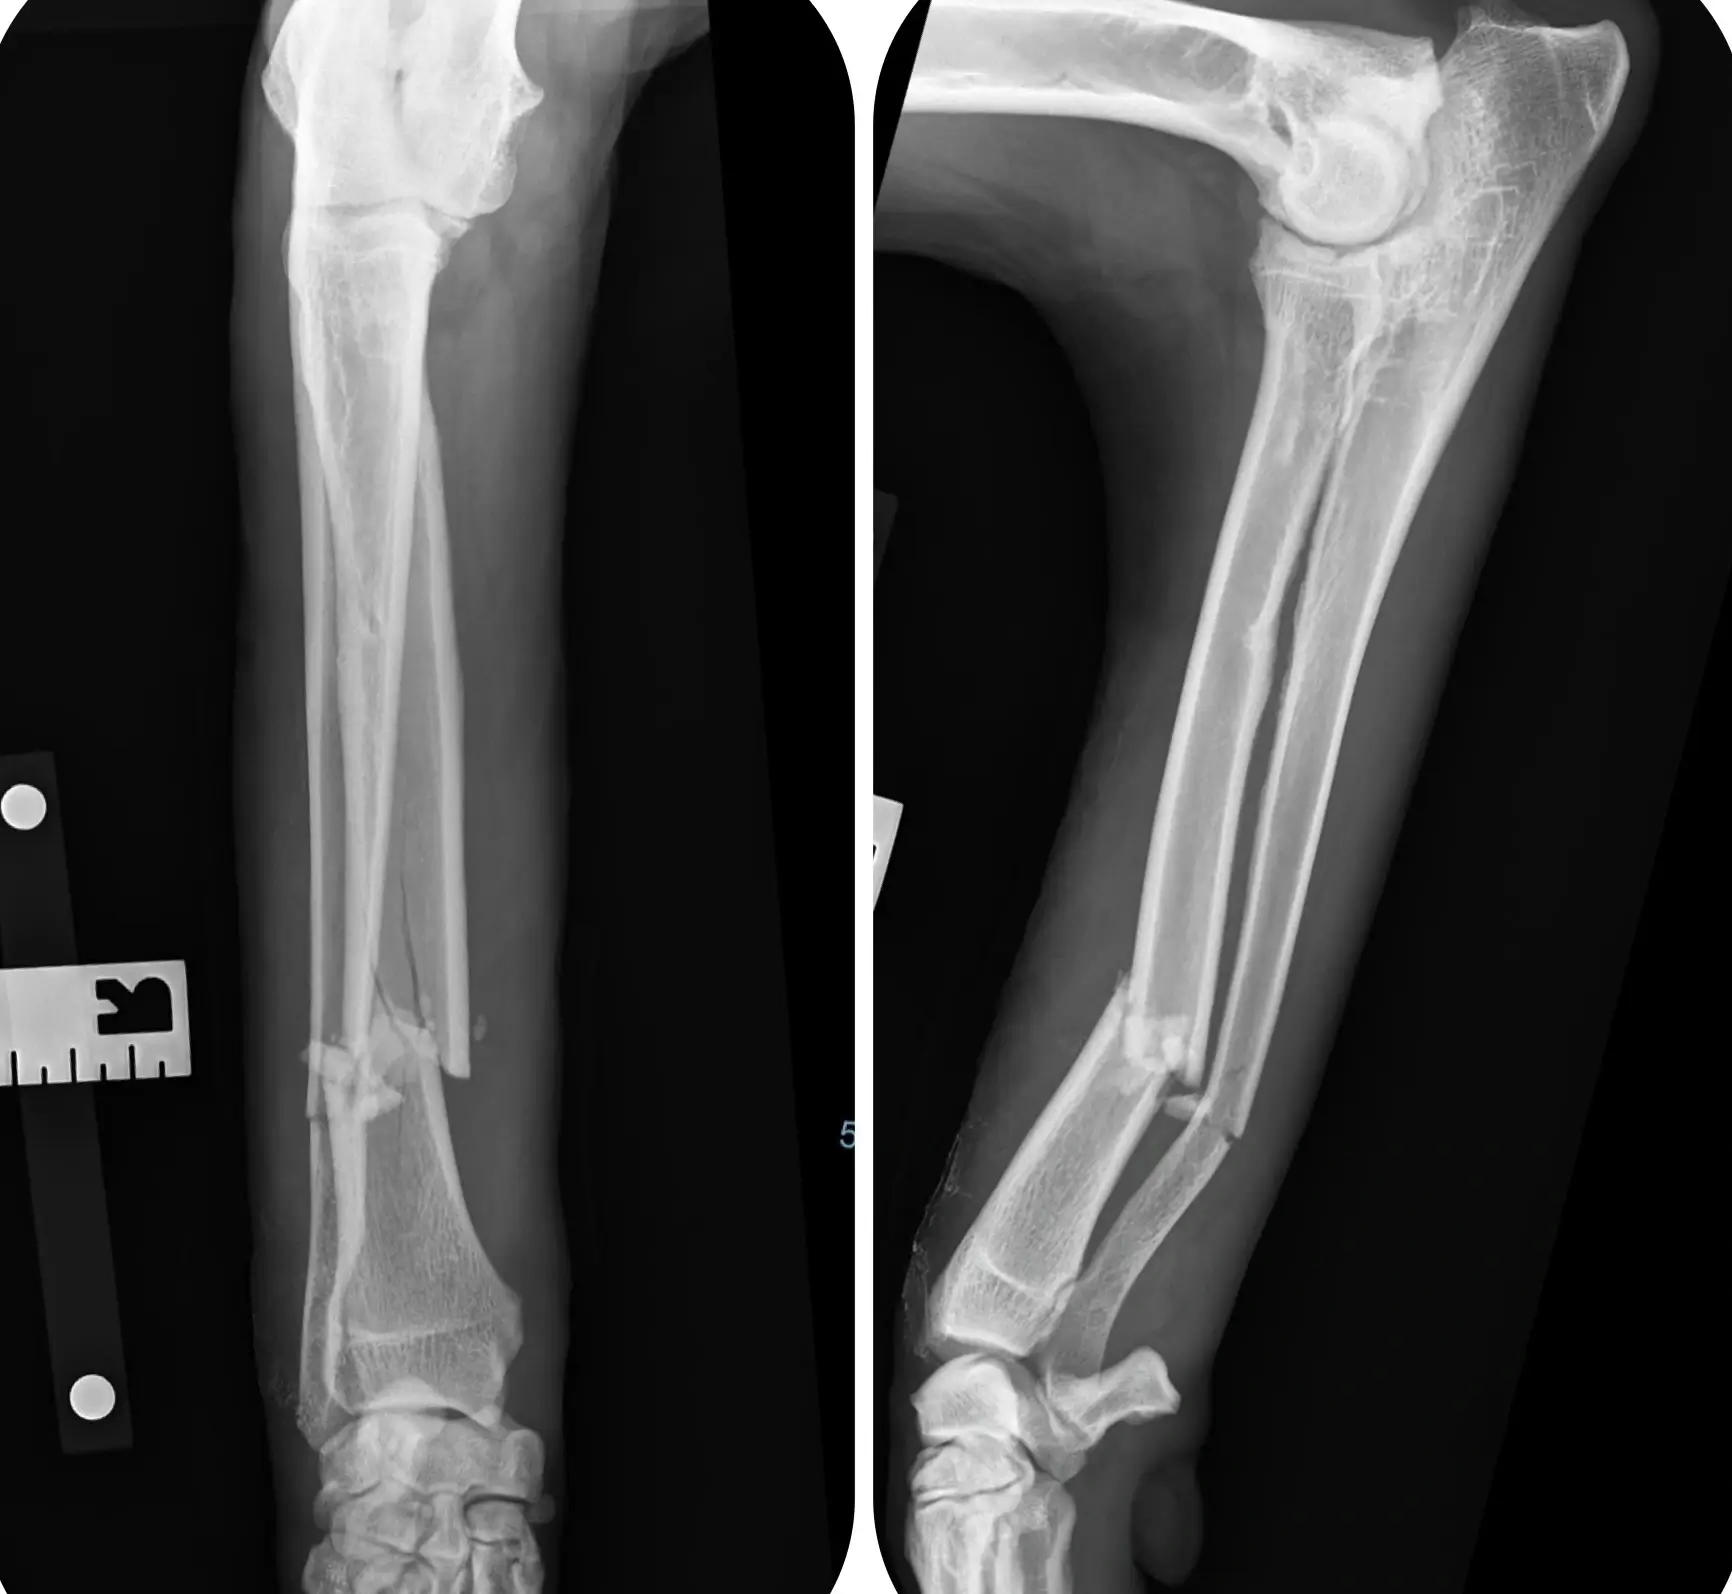

X-Ray

• Fractures

• Trauma

• Digital radiography (X-rays) for fast and accurate assessment of musculoskeletal, pulmonary, gastrointestinal, and urogenital disorders.